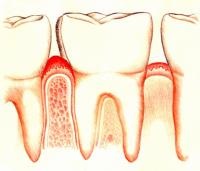

Először is kezdődik egy kis duzzanat és fájdalom a fogak, majd kiderül egy fogínyvérzés fogmosás közben és a rossz lehelet. Ez vezet a különböző betegségek a fogíny és a veszteség a tej, és még zápfogak. Sajnos ínybetegségek nem csak azokat a következményeket.

Ahhoz, hogy a berendezés megfelelően, meg kell értenünk, hogy a „rossz baktériumok”, ami ezeket a betegségeket, amelyek mentén az íny alá, és különösen a zápfogak. Ezért kell azokra a területekre a szájban, ahol fennáll a veszélye a baktériumok kiépítése, és tisztítsa meg alaposan.

Jelek a korai stadii- duzzanat, bőrpír és érzékenysége az íny. Tudatlan emberek nem értik, hogy az ilyen tünetekkel alaposan meg kell tisztítani azokat a területeket, amelyek gyulladt, mert félt a rossz közérzet. Ez lehetővé teszi, hogy a fertőzés a folytatáshoz akadálytalan.